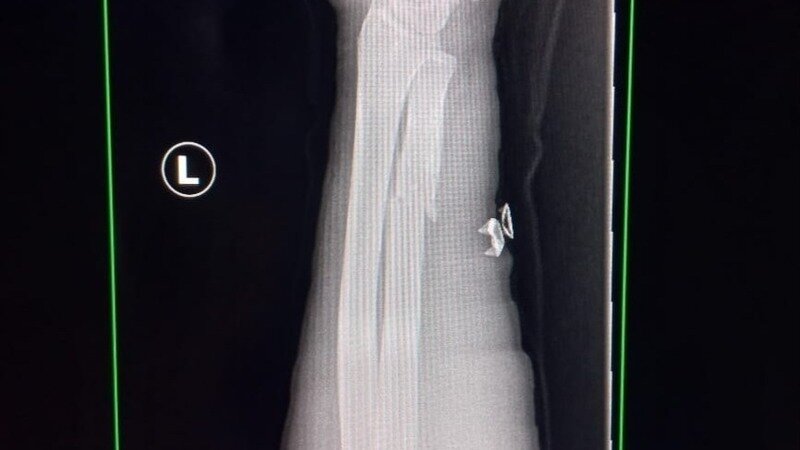

Neuigkeit zur PetitionExpedite Clearance for Mr. Hani A A Abualqaraya to Exit GazaMy Hanis leg bone and arm bones are broken we need immediate evacuation and ceasefire -rafah attack

He's had his scans both his arm and leg of the left side are broken.

He needs immediate evacuation.